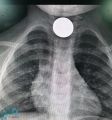

استخراج عملة معدنية من مرئ طفل بمستشفى جنوب القنفذة